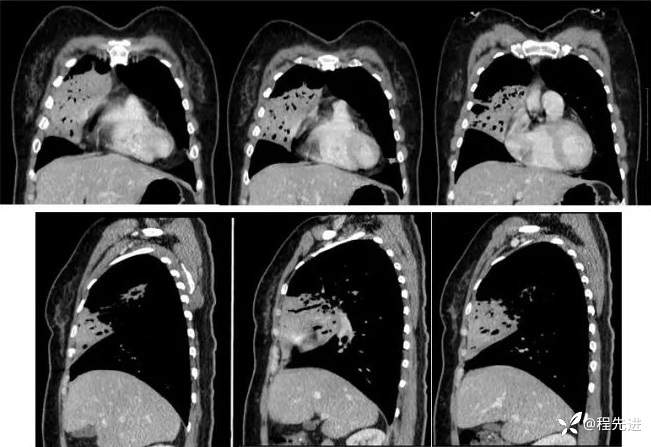

直接CT增强: